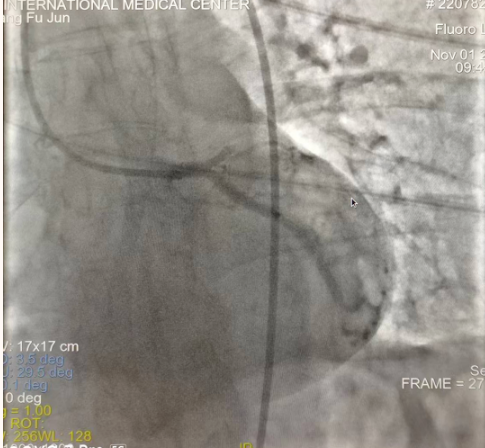

閉塞的血管再通時間取決于急救時長、轉(zhuǎn)運時長和治療時長,在前兩方面,醫(yī)院已為患者爭取了最短時間?;颊呒覍龠h在陜北,雖然已在趕來的路上,但最快抵達西安也要3小時,在與患者家屬電話溝通同意急診手術(shù)后,醫(yī)療總值班代家屬簽字,康曉軍在請示心臟病醫(yī)院王海昌院長及心臟內(nèi)科CCU尚福軍主任后,積極進行術(shù)前準(zhǔn)備。在沒有家屬陪同、沒有交費、沒有辦入院手續(xù)的情況下,患者經(jīng)胸痛中心綠色通道被送往心臟冠脈介入手術(shù)室,打通了完全閉塞的心臟前降支近段血管。